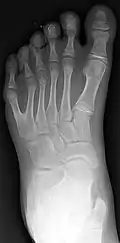

Classification is performed by using x-ray imaging to see the bone structures.[16]